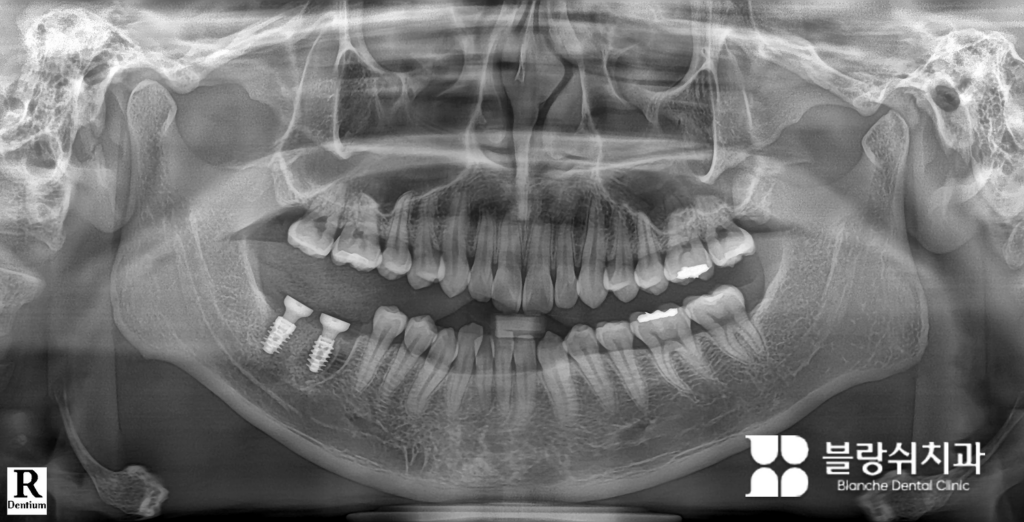

스트라우만 BLX 임플란트 즉시 식립 사례

이 사례는 우측 하악 제1·2대구치 발치 후 진행한 케이스인데요. 정확히는 발치한 직후, 즉시 임플란트를 식립한 경우입니다. 발치와 동시에 임플란트를 심는 즉시 식립은 수술 난이도가 높은 편에 속하며, 초기 고정력과 임플란트 형태 설계가 결과를 크게 좌우합니다. 이 케이스에서 사용된 제품이 바로 스트라우만 BLX 임플란트입니다.

엑스레이를 확대해 보면, BLX 임플란트 특유의 날카롭고 공격적인 나사선 형태를 확인할 수 있습니다. 일반적인 임플란트보다 뼈를 더 단단히 파고드는 구조로 설계되어 있어, 발치와 같이 불안정한 환경에서도 초기 고정력 확보에 유리합니다. 이 케이스는 “왜 이 상황에서 BLX를 선택했는가”라는 판단 기준을 보여주는 대표적인 즉시 식립 사례입니다.